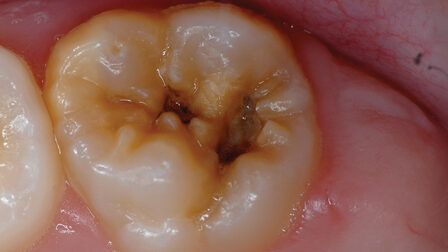

Chemo-mechanical caries removal: Effectively eliminating decay and stress

The introduction of minimally invasive dentistry (MID) has revolutionized the management of dental caries by emphasizing the preservation of sound dental tissue capable of remineralization.1-3 This philosophy forms the foundation of chemo-mechanical caries removal (CMCR), which targets the selective removal of infected dentin while preserving the healthy, potentially remineralizable tissue.4 CMCR is a pain-free, conservative approach that … Read more